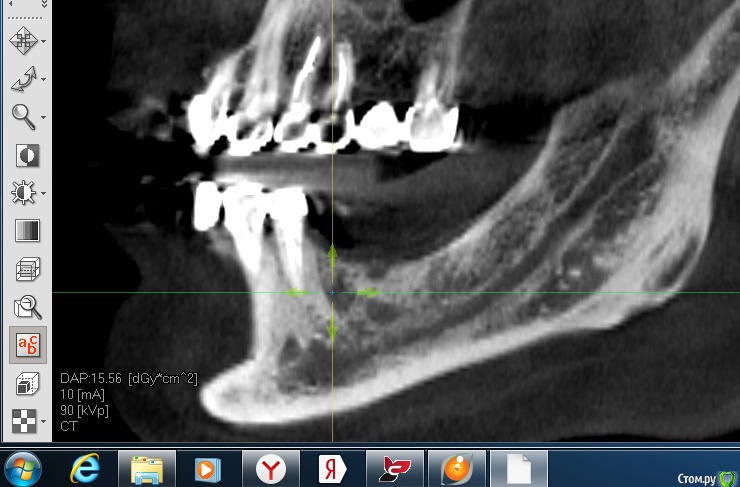

alboard Опубликовано 22 сентября, 2017 Поделиться Опубликовано 22 сентября, 2017 Что бы темы не плодить, спрашиваю тут. Было удаление 36го зуба в марте этого года. Удалял не я. Со слов пациента: после удаления в лунку засыпали БиоОсс. Кт свежее. Ожидать кашу? Ну и повторюсь, что в таком случае делать? Ссылка на комментарий

Павел7809 Опубликовано 21 октября, 2017 Поделиться Опубликовано 21 октября, 2017 Что бы темы не плодить, спрашиваю тут. Было удаление 36го зуба в марте этого года. Удалял не я. Со слов пациента: после удаления в лунку засыпали БиоОсс. Кт свежее. Ожидать кашу? Ну и повторюсь, что в таком случае делать?Ставьте спокойно 2 Ссылка на комментарий

Duke 390 Опубликовано 10 апреля, 2018 Поделиться Опубликовано 10 апреля, 2018 Удалял 24 зуб.после удаления- отсутвие вестибулярной стенки.отслоил слизистую вестибулярно через лунку.уложена мембрана duo teck.в лунку sure oss ( алло), лунка укрыта мукографт.швы.снимки через 2.5 мес.имплантат с торком 15 под заглушку. 1 Ссылка на комментарий